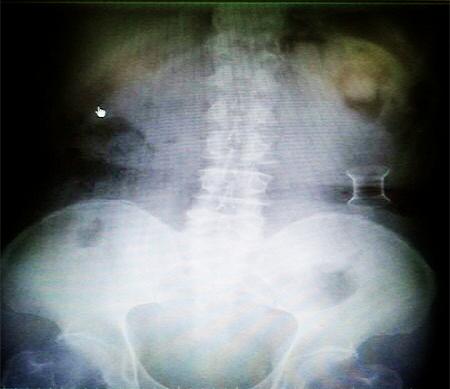

受試患者在結(jié)腸端端吻合術(shù)中,使用我司新研制產(chǎn)品達到了理想的預期效果。患者術(shù)后7天、14天X光片顯影,可降解腸道支架均能按研制設(shè)計的預期時間節(jié)點保持應(yīng)有強度,術(shù)后21天X光片顯示可降解腸道支架已完全破碎,并排出體外。在整個試驗過程中,病患無任何不良反映,耐受良好。